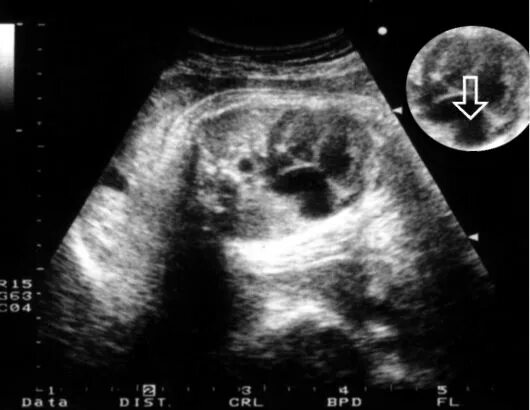

Узи аномалий